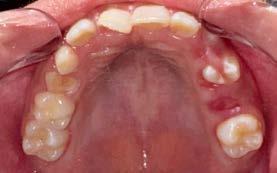

Paciente femenina de 10 años de edad, aparentemente sana, acude acompañada de su madre a la Clínica Estomatológica Tepepan, turno vespertino, de la Universidad Autónoma Metropolitana. Al examen clínico intraoral se observó el O.D. 2.1 con irregularidades en el esmalte, localizadas en los tercios cervicodistovestibular, mediodistovestibular e incisodistovestibular, con múltiples porosidades y coloración amarillenta (Figura 2).

En el examen radiográfico se observó una zona radiolúcida a nivel coronario del O.D. 2.1 en los tercios antes referidos; asimismo, se identificó una porción radicular disminuida en comparación con el O.D. 1.1, así como curvatura radicular (Figura 3).

Figura 1.

Figura 2.

Con base en la evaluación clínica y radiográfica, se estableció el diagnóstico pulpar de diente vital, sin signos de inflamación ni patología periapical. Asimismo, la superficie vestibular presentó integridad estructural, sin evidencia de desmineralización o lesión cariosa, clasificada como ICDAS 0 (Figura 1). Considerando estos hallazgos, se indicó un abordaje conservador mediante ameloplastia selectiva, con el objetivo de regularizar las

Figura 3.

Figura 4.

Finalmente, se realizó el contorneado anatómico, pulido y acabado de la restauración, logrando una integración funcional y estética con los tejidos dentarios adyacentes (Figura 4 y 5).

En el caso clínico analizado, se identificó hipoplasia en el O.D. 2.1, con manifestaciones clínicas que incluyeron manchas de coloración blanca y amarillo-parda, así como defectos estructurales compatibles con pérdida de tejido adamantino. Estas características son

Figura 5.